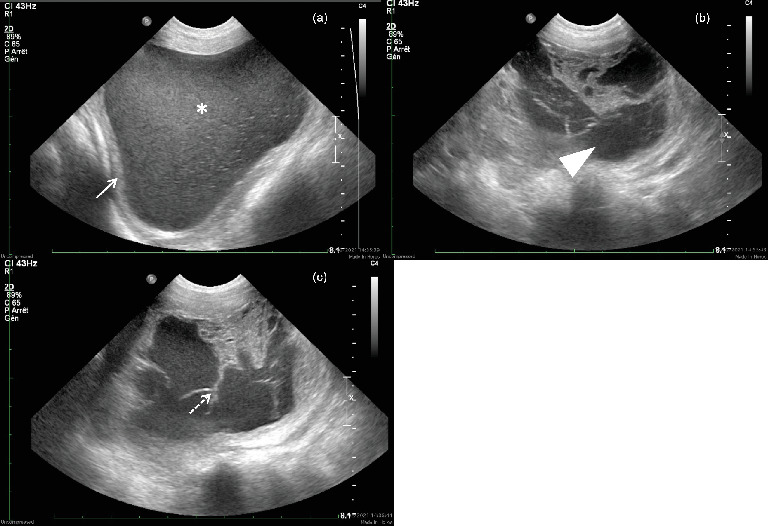

An 11-year-old neutered female Labrador was presented with dyschezia and dysuria associated with a large perineal mass that had been present for 2 years. Computed tomography (CT) revealed a large bilobed, cavitated mass localized ventrally to the rectum and dorsally to the urethra at the level of the vagina, with hypoattenuating contents and a contrast-enhancing peripheral wall. Surgical excision was performed and confirmed the cystic nature of the mass. Histopathological findings were compatible with a benign vaginal cyst, most likely originating from the Müllerian or paramesonephric ducts. The CT provided relevant information for surgical planning and enabled accurate assessment of the mass's location, extent, and relationship with adjacent structures.

摘要一位11岁的绝育拉布拉多犬,因出现2年的会阴大肿块而导致排尿困难。计算机断层扫描(CT)显示一个大的双叶状空洞肿块,位于直肠腹侧和阴道水平的尿道背侧,内容物低衰减,周围壁增强。手术切除后证实肿块为囊性。组织病理学检查结果符合良性阴道囊肿,最可能起源于勒氏管或肾旁管。CT为手术计划提供了相关信息,并能够准确评估肿块的位置、范围以及与邻近结构的关系。